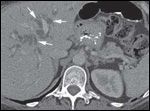

DR. PAUL RUSS: The initial CT scan of the abdomen with intravenous and oral contrast revealed a 2.7-cm, hypodense, hypovascular, solid mass in the head of the pancreas and also involving the uncinate process. In addition, there was dilatation of the pancreatic, intrahepatic and extrahepatic ducts without any evidence of distant metastatic or lymph node involvement. However, the second CT scan done, at the time of her clinic visit, showed post-surgical changes with an ill-defined soft tissue mass in the operative bed. There were also five new hypodense lesions in the liver, with the largest lesion in the anterior segment measuring 1.3 × 1.5 cm. There were two lesions in the dome, measuring 1.1 cm and 8 mm, along with two additional subcentimeter lesions in the right lobe (Figures 1A-1D, 2).

DR. PAUL RUSS: Because pancreatic adenocarcinoma is typically hypovascular compared to background pancreas and liver, the primary neoplasm is depicted as hypodense to the pancreas, and metastases as hypodense to the liver. However, some pancreatic adenocarcinomas remain occult, even with the use of advanced CT techniques, and in those cases the diagnosis can sometimes be surmised by using indirect, secondary signs like pancreatic and/or bile duct dilatation, and post-obstructive pancreatic atrophy. In this case, we see one of the typical hypodense lesions consistent with metastatic pancreatic cancer.